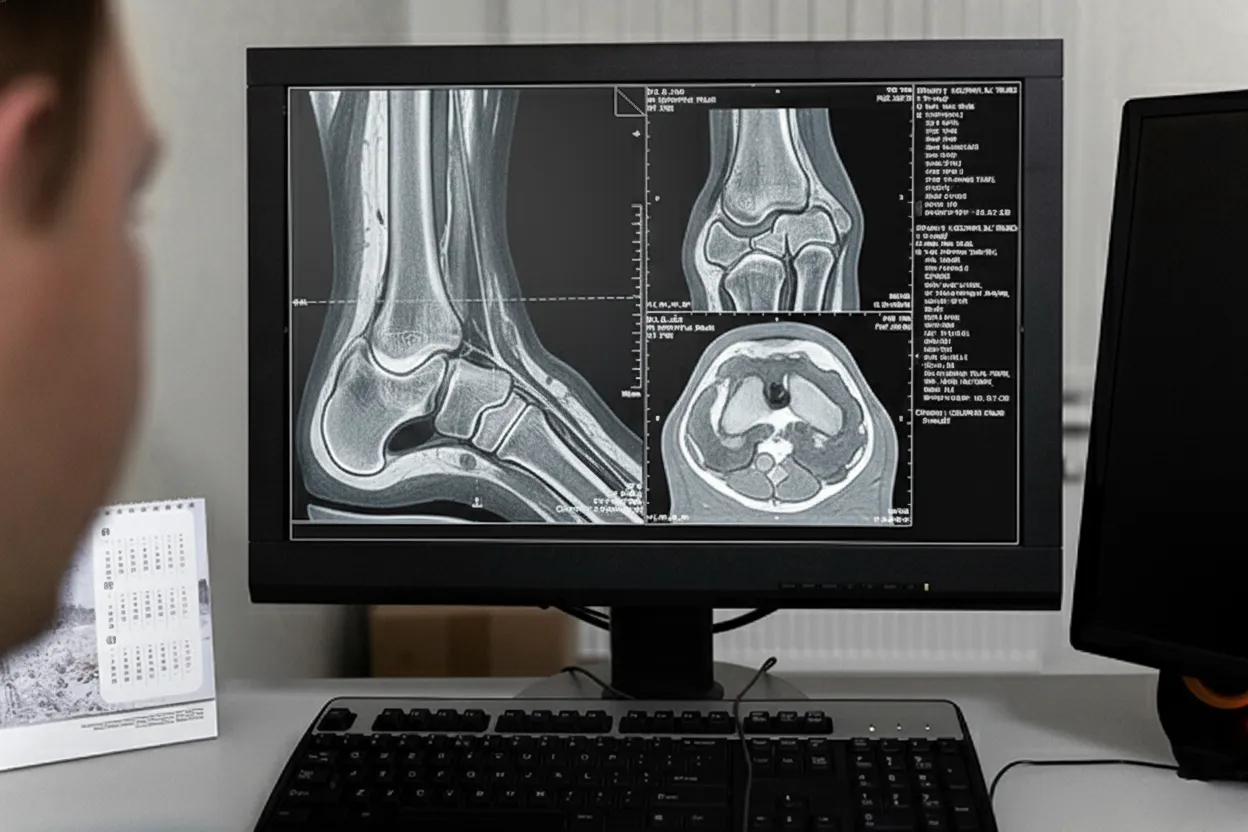

Visualizing the damage